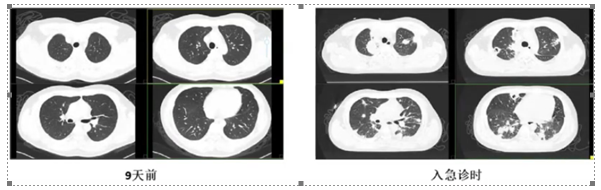

图3 患者颈部CTV

该患者院内及出院后1个月给予低分子肝素抗凝,之后改为利伐沙班,共抗凝半年左右时间。之后停药。后续复查患者情况稳定,血栓无变化。